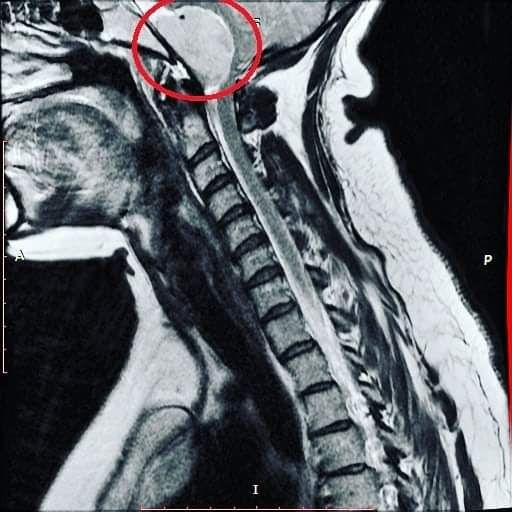

Educator, partner, parent, traveler, trivia buff, data enthusiast, SF Giants fan, host of the inoperable brain tumor known as Donald Lump. She/her. On Nisenan land. #maskup 💜

Meet Donald Lump, my foramen magnum meningioma. A thread.